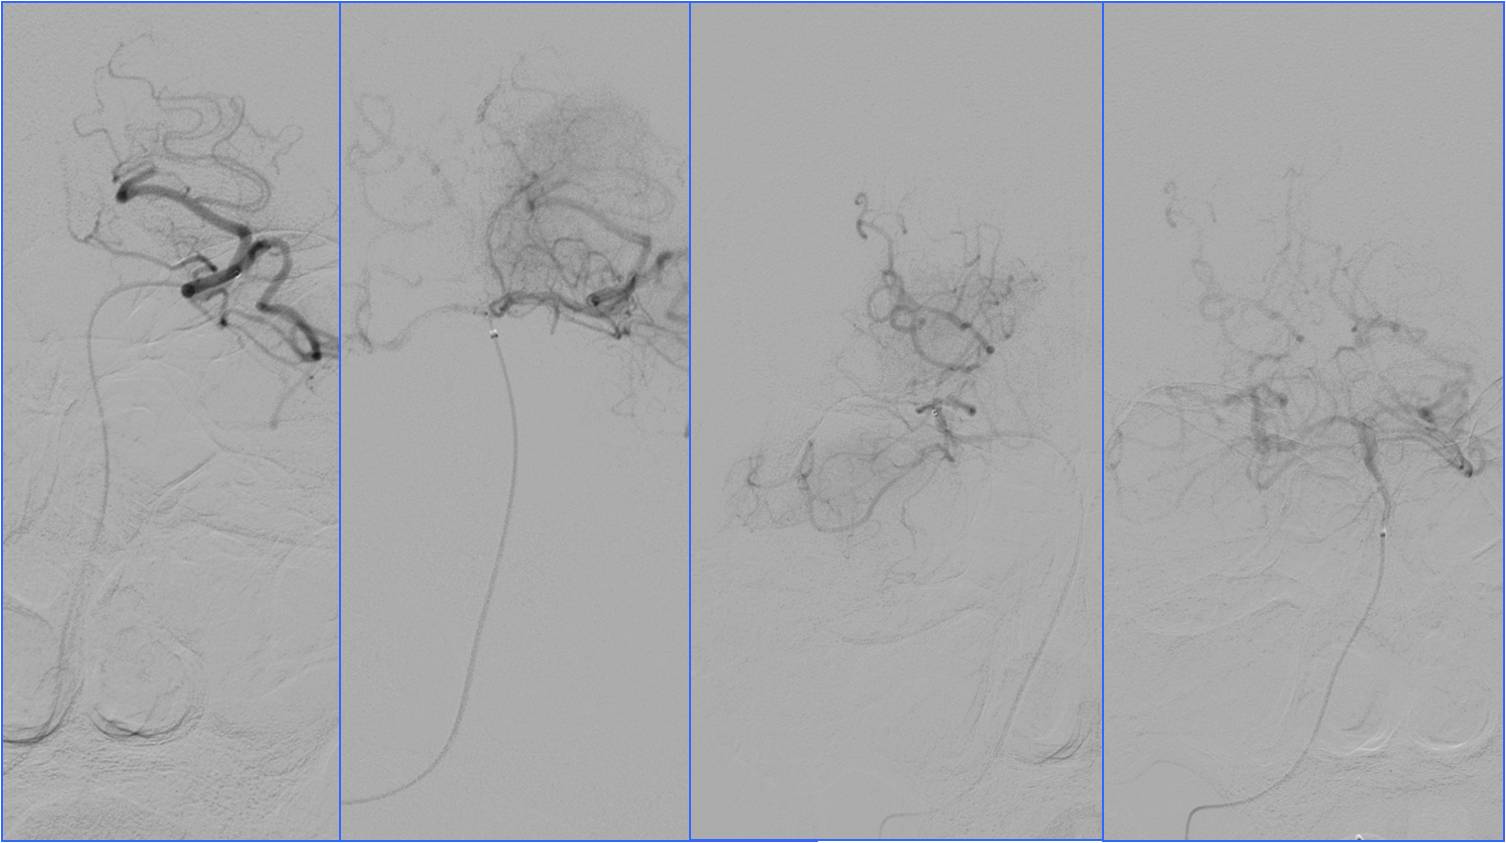

▼于基底动脉远端及双侧大脑后动脉,分次给予阿替普酶共计5mg。

▼溶栓后MRI